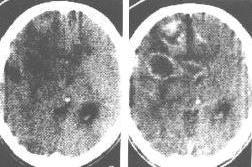

| Ⅲ级星形细胞瘤。CT平扫(左图)示右颞顶部低、等混合密度灶,边界欠清。增强(右图)示病灶呈花圈状增强,周围伴中度水肿。